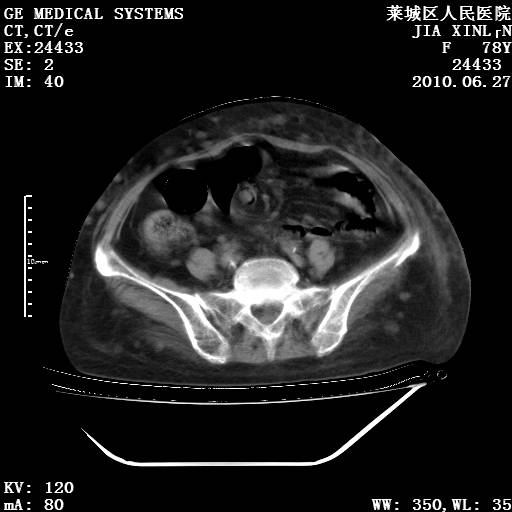

以下是引用胡宇在2010-7-2 19:11:00的发言:[br]神经纤维瘤的特点为:肿块呈多发性、数目不定,少的几个,多的可成百上千难以计数。小的如米粒,大的似拳头,甚至可达十数公斤以上。可松弛地悬挂于皮表,皱褶及松弛可致畸形明显。神经纤维瘤沿神经干的走向生长时呈念珠状,或蚯蚓块状形结节。此外神经纤维瘤皮肤可出现咖啡斑,大小不一,形如雀斑小点状,或大片状,分布与神经纤维瘤肿块的分布无关。肿瘤数目不多的患者,皮肤色素咖啡斑状沉着是纤维神经瘤的重要诊断之一。 本病多发于躯干,有时出现于四肢及面部,患者常合并许多疾病应予重视加以区别。 [br] [br] [br] [br]lyb999说 [br]